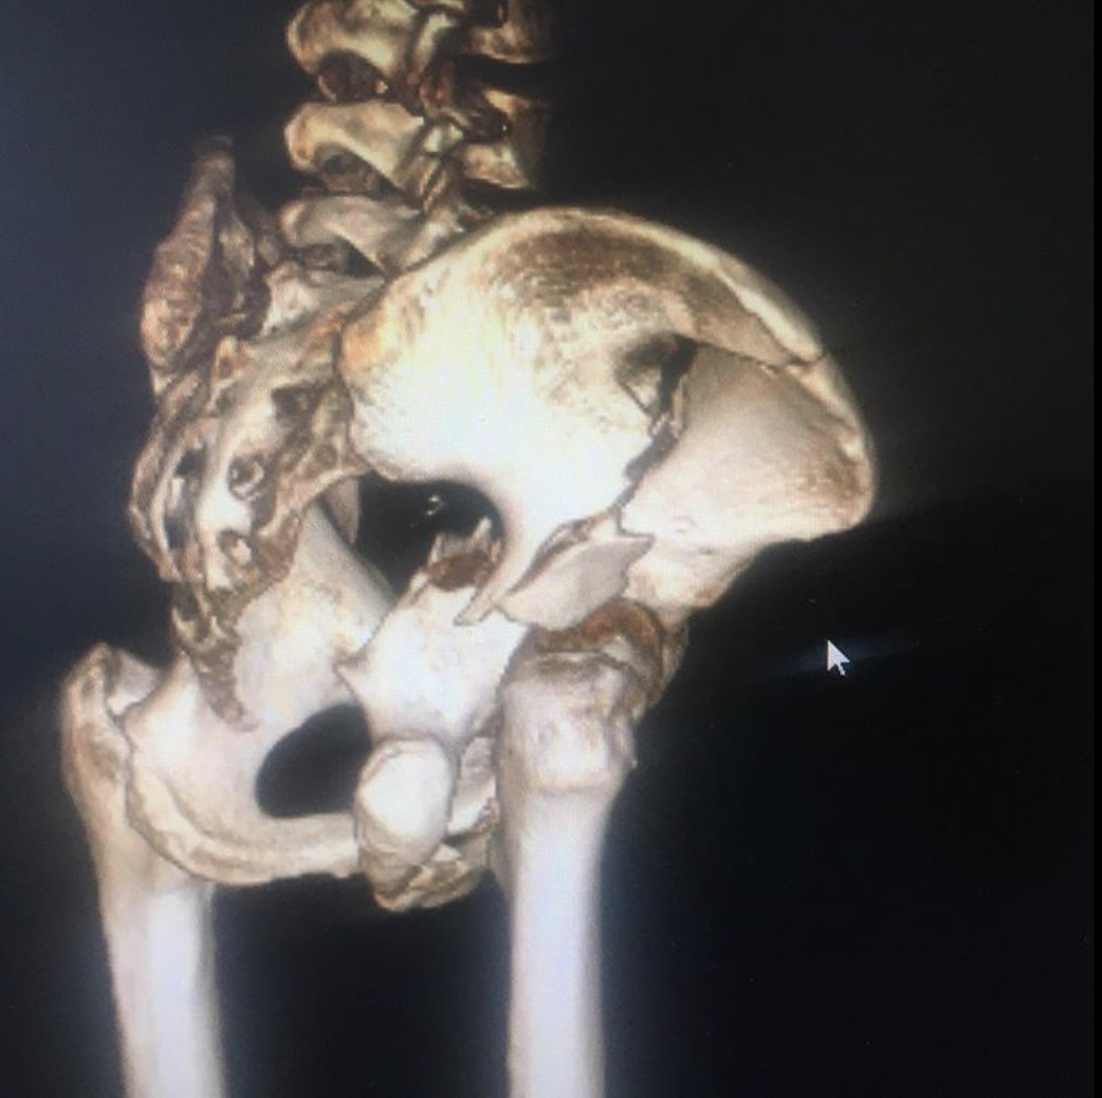

Ещё один случай тяжелой травмы вертлужной впадины с разнонаправленным смещением отломков.

Перелом вертлужной впадины со смещением – сложный перелом в области ямки тазобедренного сустава. Обычно возникает в результате воздействия сильной кинетической энергии, удара или падения, в группу риска входят спортсмены, частая травма при автомобильных авариях.

Сложность данного травматизма в длительном восстановительном периоде, высокой вероятности возникновения посттравматического коксартроза, который приводит к инвалидности пациента. Лечение перелома со смещением хирургическое в случае наличия вывиха сустава, крупных отломков костей, существует риск неполного восстановления двигательной функции.